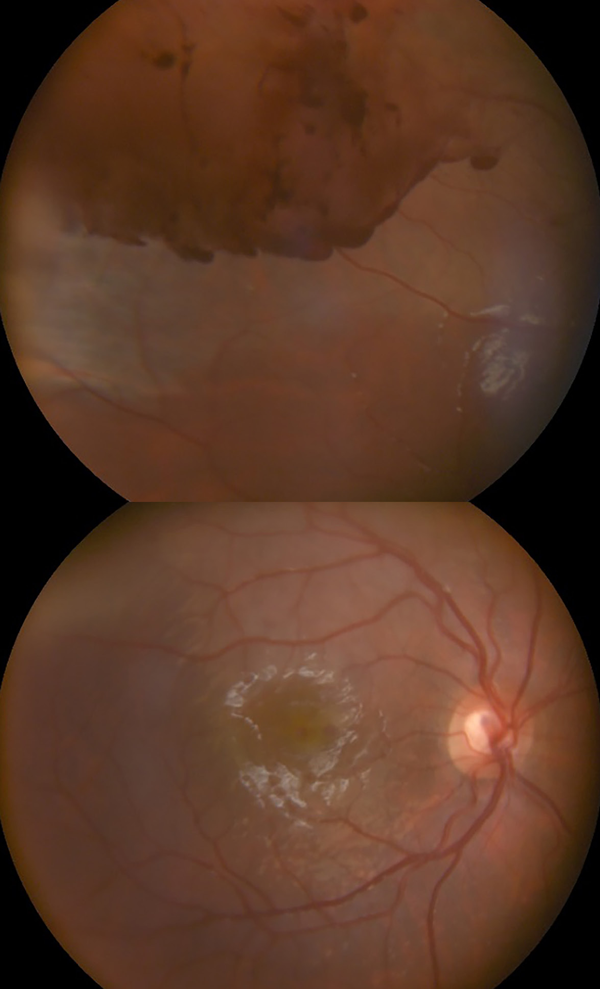

En el fondo del OD se observa zona de conmoción retinal y hemorragia superior sin observarse presencia de desgarros, y además la retina se ve aplicada. Al mismo tiempo se realiza retinografía para documentar tales observaciones (fig. 1).

Figura 1. Retinografía donde se observa hemorragia subretinal superior y edema macular.